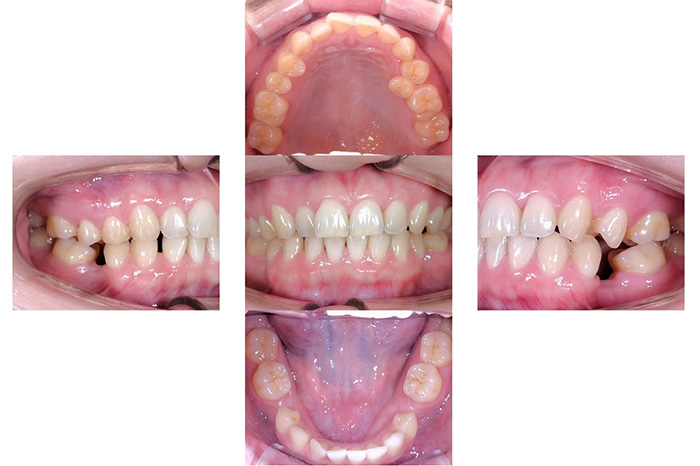

インビザラインによる全体矯正後に補綴治療を行い、咬合と審美性を総合的に改善した症例です。

まずマウスピース型矯正装置(インビザライン)により歯列および咬合関係を整え、その後、必要部位にジルコニア補綴を行いました。

矯正のみ・補綴のみではなく、両治療を組み合わせることで機能性と審美性の両立を目指した包括的治療です。

奥歯の噛み合わせと前歯の歯並びを同時に改善した症例(インビザライン+ジルコニア)

患者様は、奥歯でしっかり噛めないことと、前歯の歯並びの乱れを気にされ来院されました。診査の結果、前歯部の叢生(歯並びの乱れ)と、臼歯部の離開咬合(奥歯がしっかり噛み合っていない状態)が認められました。また、臼歯部には古い金属修復物が装着されており、機能面だけでなく審美面においても改善が必要な状態でした。

【治療後】

前歯の歯並びが整い、見た目の改善が認められました。また、奥歯でしっかり噛める状態となり、咬合機能の回復が得られています。

本症例では、歯並びの改善だけでなく、噛み合わせの回復と審美性の向上を同時に行っています。当院は一般歯科と矯正治療の両方に対応しているため、矯正治療後に別の医療機関で補綴治療を行う必要がなく、一貫した治療計画のもとで治療を完結することが可能です。また、奥歯の噛み合わせを矯正治療のみで改善する場合、治療期間が長くなることがありますが、本症例では補綴治療(アンレー)を併用することで、比較的短期間で咬合の改善を行いました。さらに、古い金属修復物をジルコニアに置き換えることで、見た目の改善と機能性の両立を図っています。